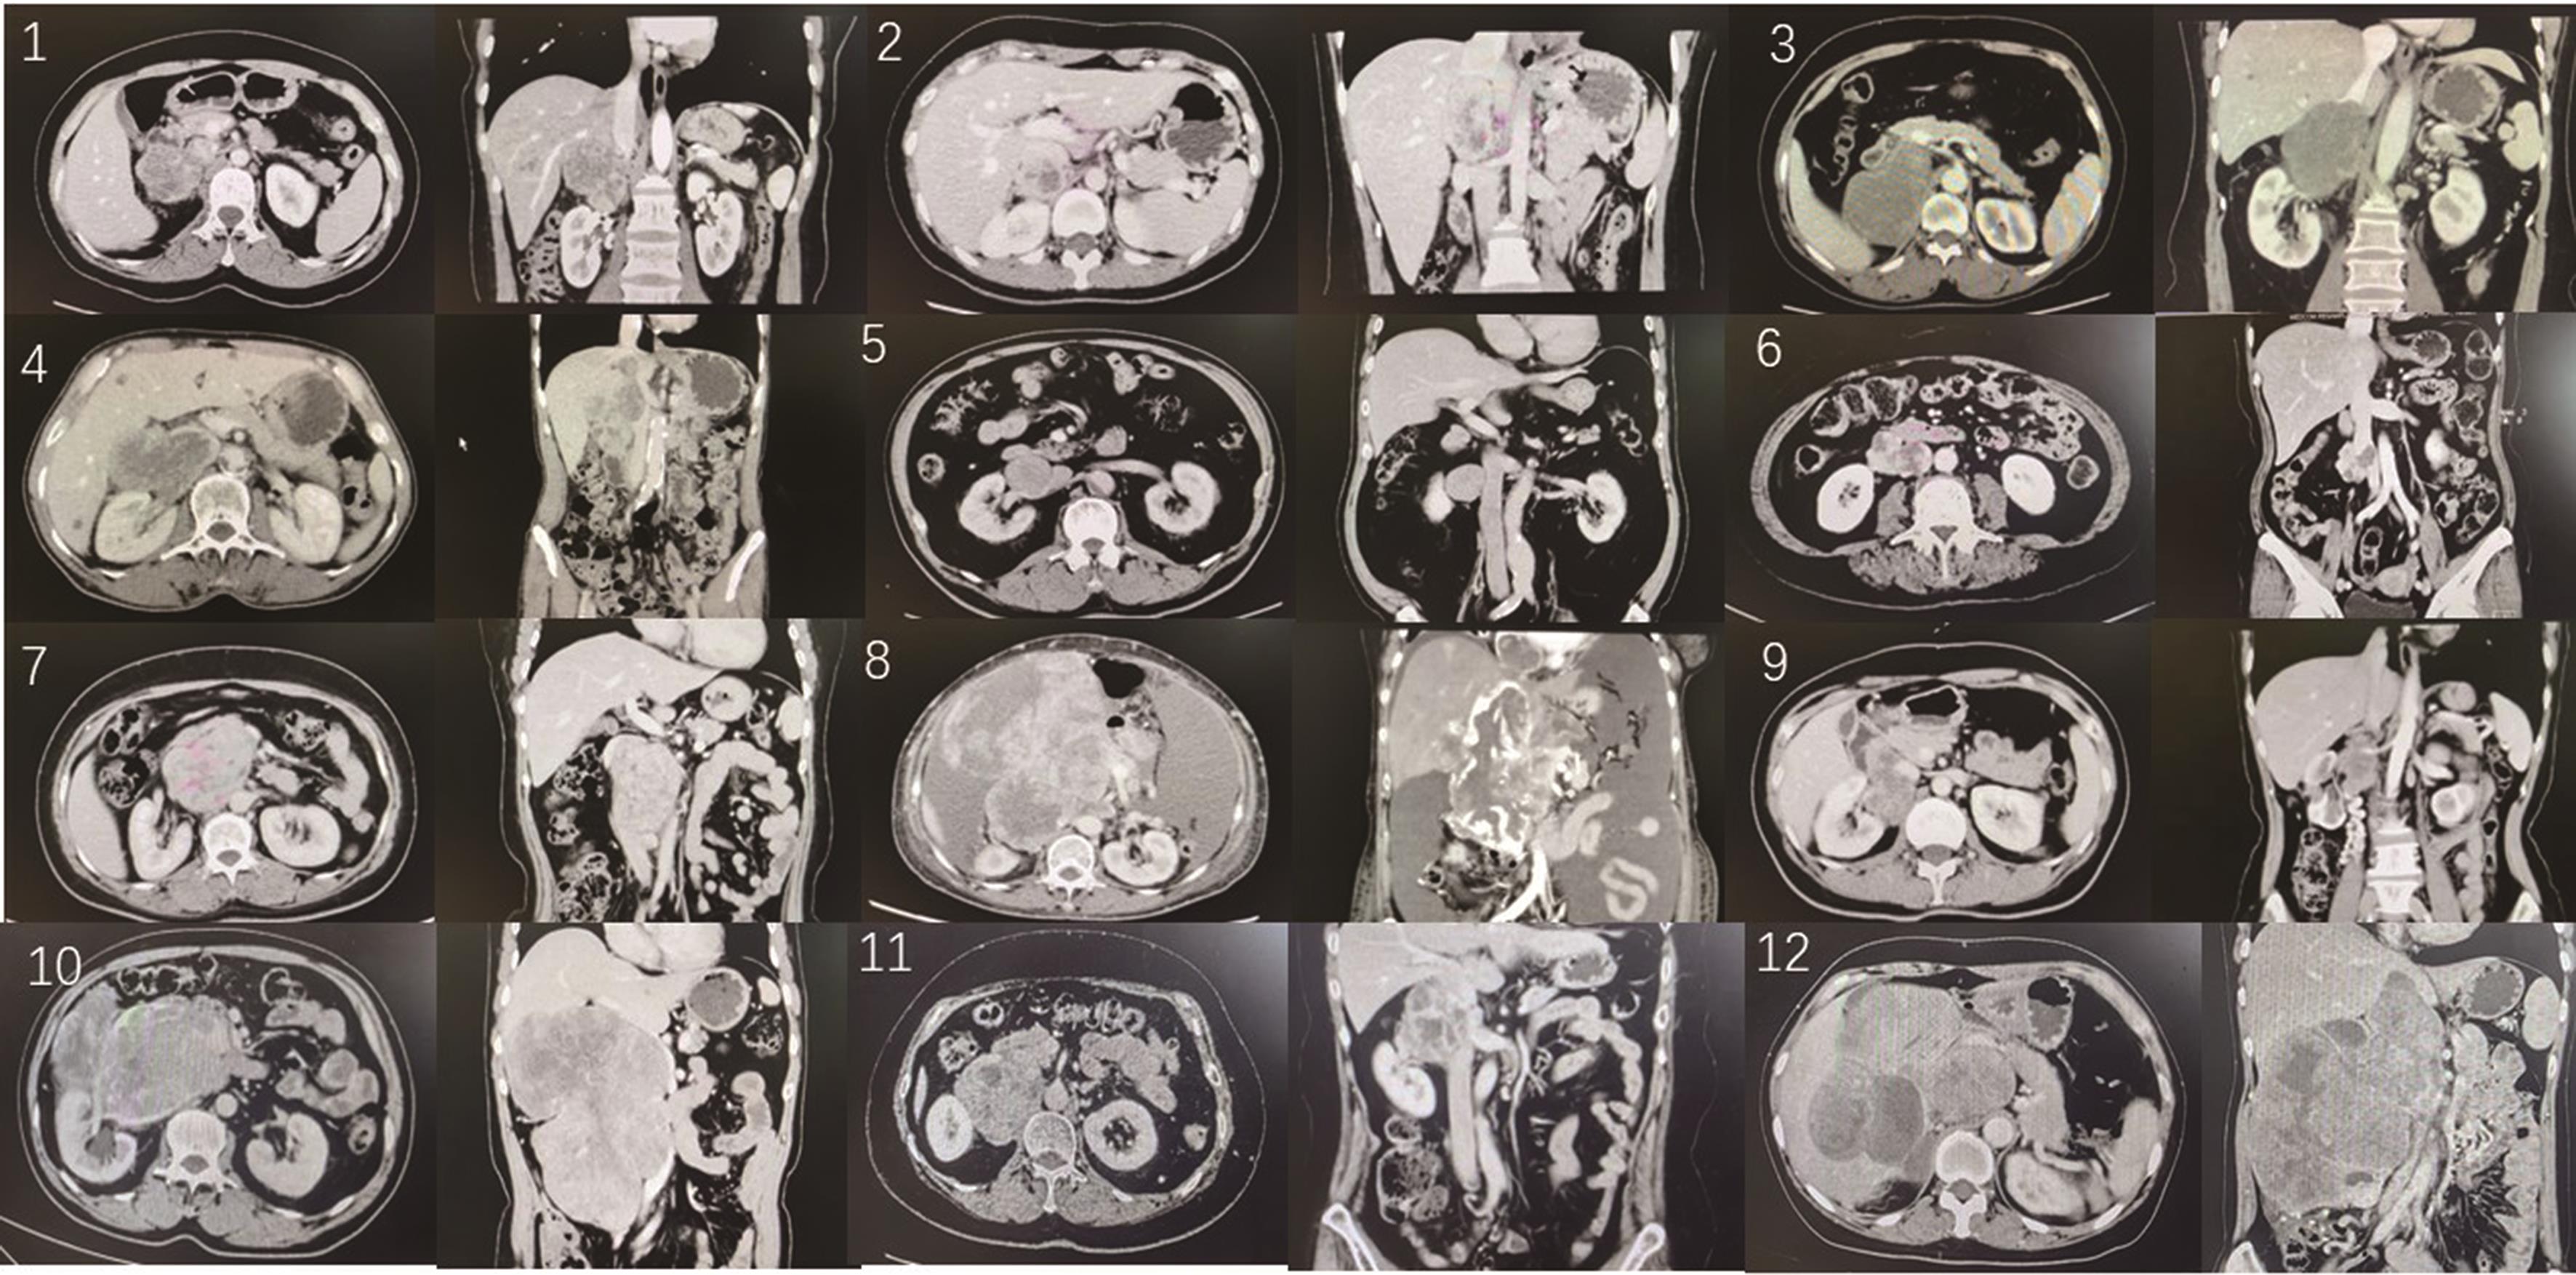

• 腹膜后血管源性平滑肌肉瘤诊疗策略

2023, 48(8):953-957. DOI: 10.13406/j.cnki.cyxb.003285

摘要 (97) HTML (38) PDF 2.06 M (597) 评论 (0) 收藏

摘要:目的 总结临床上少见的腹膜后血管源性平滑肌肉瘤的诊断和治疗策略。方法 自2018年7月至2023年4月,纳入12例腹膜后血管源性平滑肌肉瘤病例,男性3例,女性9例。平均年龄55.2(32.0,69.0)岁。全部为右侧。临床症状包括腰腹部不适、下肢麻木、下肢水肿及腹水。术前误诊为肾上腺皮质癌或副神经节瘤4例,1例未手术行穿刺病理明确。11例手术病例中,后腹腔镜手术4例,其中1例中转为开放;开放手术5例;机器人辅助腹腔镜手术2例。所有病例术中均需进行下腔静脉相关操作,包括夹闭下腔静脉完成右肾静脉修补1例;下腔静脉单纯缝合3例;下腔静脉壁部分切除后单纯修补2例;下腔静脉壁生物补片修补2例;下腔静脉切断再吻合1例;下腔静脉节段性切除2例。结果 肿瘤平均大小10.6(4.2,22.0) cm,平均手术时间268(151,467) min,平均出血量715(20,1 550) mL,术中输血8例,5例同时切除右肾,1例切缘阳性,术后延迟腹膜后出血2例。最终证实,1例平滑肌肉瘤来源于肾上腺中央静脉,2例来源于肾静脉,9例来源于下腔静脉。6例形成下腔静脉内瘤栓。病理显示肿瘤由梭形细胞组成,核分裂象易见。免疫组化所有病例SMA 阳性;8例Desmin阳性;Ki-67阳性表达率为20%~80%。平均随访21.6(1.0,54.0)个月。死亡3例;术后复发转移并生存4例;5例无复发,其中3例随访超过2年。结论 腹膜后血管源性平滑肌肉瘤术前容易误诊,术中需处理下腔静脉。手术难度大,应根据情况采用多种手术方式,开放手术首选,后腹腔手术镜选择需谨慎。肿瘤恶性度高,易复发。